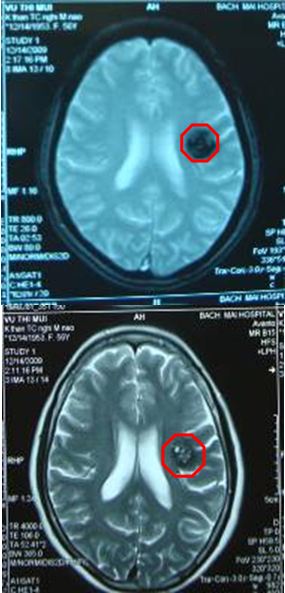

Trường hợp thứ 1: Bệnh nhân Vũ Thị T., nữ 33 tuổi, được chẩn đoán là u máu thể hang vùng thân não đường kính 14mm từ tháng 10 năm 2008; được điều trị xạ phẫu bằng dao gamma quay tháng 11 năm 2008. Cho đến nay bệnh nhân hoàn toàn khỏe mạnh, sinh hoạt và lao động bình thường.

Khối u máu thể hang vùng thân não trước điều

trị: kích thước 14mm (hình màu đen bên trong hình

đỏ). Trên lâm sàng bệnh nhân đau đầu nhiều,

chóng mặt, không đi lại được, lác trong mắt trái.

Tổn thương tan biến hoàn toàn sau điều trị

6 tháng. Trên lâm sàng bệnh nhân hết

đau đầu, hết chóng mặt, đi lại được, hết

lác trong mắt trái. Sinh hoạt bình thường